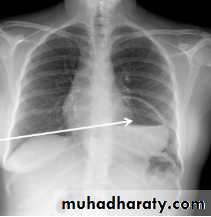

Large hiatus hernia, seen with fluid in stomach